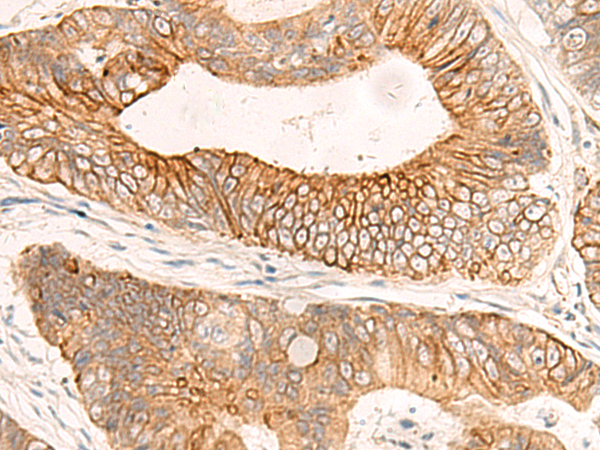

ELISA, IHC |

IHC positive control: |

Human colorectal cancer and Human tonsil |

IHC Recommend dilution: |

40-200 |